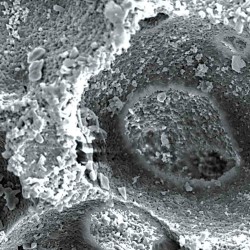

Maxresorb® inject es una pasta ósea sin endurecimiento y lista para el uso compuesta de gel de nano-HA de base acuosa y partículas de Maxresorb®. Debido a su composición específica, las propiedades viscosas de maxresorb® inject permiten una forma, moldeado y ajuste perfectos y una completa adhesión a la superficie ósea circundante del defecto.

Maxresorb® inject es una pasta ósea sin endurecimiento y lista para el uso compuesta de gel de nano-HA de base acuosa y partículas de Maxresorb®. Debido a su composición específica, las propiedades viscosas de maxresorb® inject permiten una forma, moldeado y ajuste perfectos y una completa adhesión a la superficie ósea circundante del defecto.

Biofuncionalidad

Las partículas de nano-HA, ofrecen una superficie muy grande para las interacciones celulares y son rápidamente reabsorbibles.

El componente nano-HA, que representa aproximadamente el 80% del material, se reabsorbe en un plazo de 6-8 semanas.

Los gránulos maxresorb ayudan a mantener el volumen a lo largo del tiempo.

Sin endurecimiento

Maxresorb inject es una masilla ósea sin endurecimiento que promueve una rápida regeneración ósea mediante el crecimiento interno de vasos sanguíneos y células a través de su estructura porosa.